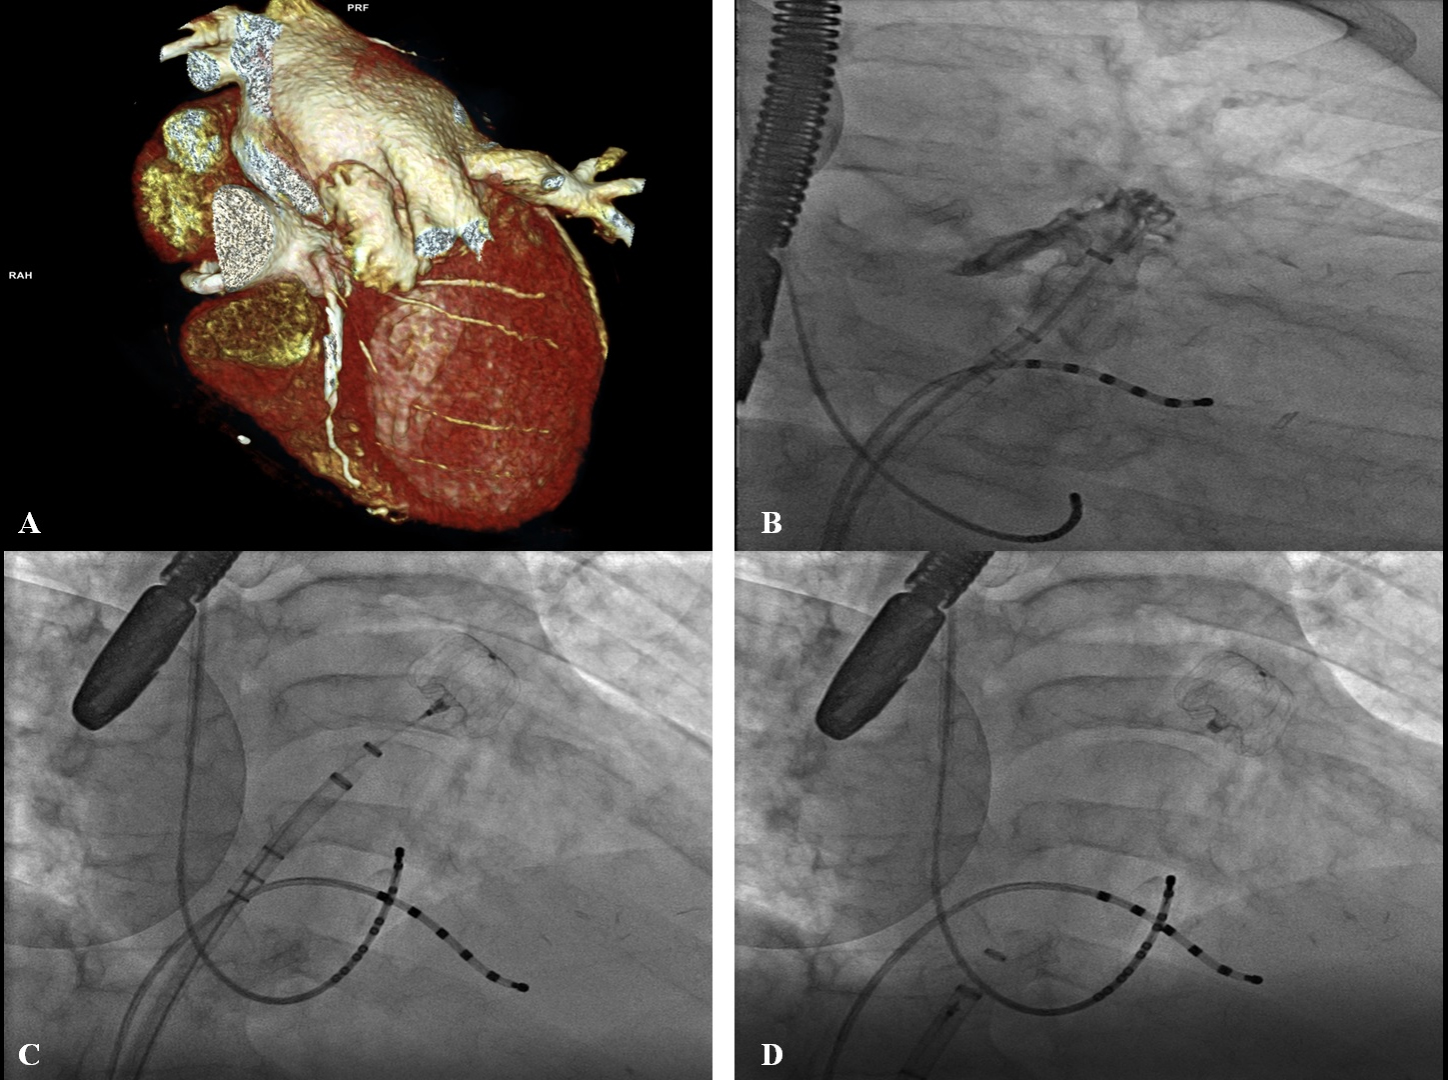

Cardiac CT has a high sensitivity (96%) and a high negative predictive value (100%) for the evaluation of thrombotic formations [17]. Once the cardiac CT images are obtained, post-processing is performed, which performs a multi-planar reconstruction of axial acquisitions. Finally, 3D reconstruction provides the ability to fully visualize the appendage and morphology. The multi-planar reconstruction also allows correct sizing of the device with different measurements that should be taken depend on the type of device selected and sometimes suggest information about different transeptal puncture position (Fig. 2) [18].

Fig. 2.Pre procedural imaging evaluation and fluoroscopic assessment of LAAO. (A) Shows a pre procedural Cardiac CT assessment of LAAO. In this case it was necessary perform transseptal puncture quite low and anterior in the fossa ovalis for this specific anatomy (high an anterior large LAA with morphology of “reverse” chicken wing). (B–D) Describe during fluoroscopy the positioning of the device with double anterior curve sheath. Catheters in coronary sinus and “His” electrophysiological anatomical location were placed to guide the transseptal puncture during fluoroscopy and device placement in this particular case.

Before the device is released, sizing should be confirmed by angiography and confirmed with TEE: correct placement (maximum device diameter must be at LAA ostium without excessively protruding into the left atrium), stability (Tug Test), correct size, proper occlusion (all lobes must be distal to the proximal portion of the device and no peri-device leaks should be visible after Color- Doppler assessment or contrast injection) (Fig. 2).